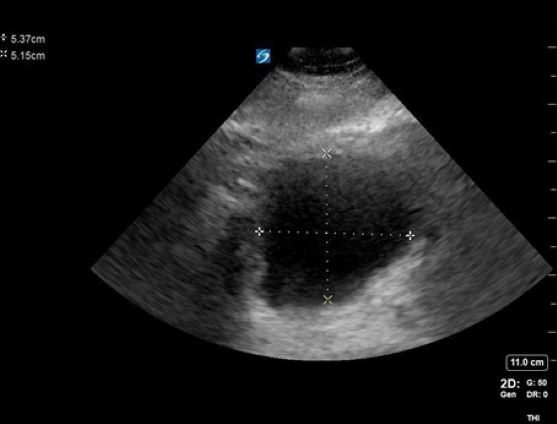

A 65-year-old male with a history of HTN, BPH, IDDM, and lumbar spinal stenosis presented to the ED with low back pain and lower extremity weakness. He denied fever, abdominal pain, and dysuria. He reports that he is able to urinate but unable to state if his urinary frequency has increased beyond “my normal prostate issues.” He notes he has fallen twice because “my legs just seem to give out on me.” On physical exam, he demonstrates 4+/5 bilateral LE strength, mild distal sensory loss, and absent patellar and Achilles reflexes. His rectal tone was equivocal. After use of a urinal, bedside POCUS was used to measure his post-void residual bladder volume:

Figure 1. A cross-sectional view of the bladder with AP and transverse measurements

Figure 3. Calculation of bladder volume using the ellipsoid method (L x W x H x 0.52 = mL)

Findings concerning for Cauda Equina were all present in this patient’s history, physical exam, and workup. Current literature defines normal post-void bladder volume in adults as < 50 mL in patients under 65 years of age, and < 100 mL in those older than 65. Two hundred milliliters or greater is generally regarded as the threshold for retention.1 In this case, the patient was just on the cusp of normal vs abnormal post-void urinary volume, but with his other clinical signs and symptoms, warranted emergency spine consultation and MRI. Imaging eventually showed severe compression of the spinal nerve roots by discs at the L2-3 and 3-4 levels, necessitating emergent decompression.

With the patient in supine position, a 2- to 5-MHz curvilinear probe is placed above the patient’s symphysis pubis in the midline position. To obtain a cross-sectional view of the bladder, the probe is oriented with the marker towards the patient’s right side. Once an image is obtained, the probe can be rotated 90 degrees to orient the marker towards the patient’s head for a long or sagittal view of the bladder. Bladder volume is obtained using the ellipsoid formula of depth x width x height x 0.52 (correction factor). Normal bladder findings include a smooth wall measuring 3-5 mm, which may decrease to 2-3 mm when filled. As discussed above, normal post-void residual volume in patients < 65 yo is < 50 mL and < 100 mL in those over the age of 65. A post-void residual of > 100 should raise suspicion about a mechanical, pharmaceutical, or neurogenic cause of retention.2-7